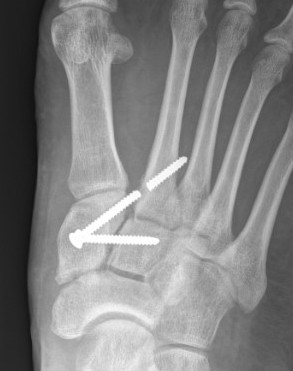

1. Diastasis of the intermetatarsal gap between the 1st and 2nd metatarsals

2. Widening of the space between the medial cuneiform and base of 2nd metatarsal

3. Second metatarsal Fleck sign - avulsion of Lisfranc ligament from base of 2nd metatarsal

4. Widening of inter-cuneiform distance

Subtle widening of the medial cuneiform - 2nd metarsal distance, and the inter-metatarsal distance

Widening of the medial cuneiform - 2nd metatarsal distance, inter-metatarsal diastasis, fleck sign, possibly increased inter-cuneiform distance

Widening of the medial cuneiform - 2nd metatarsal distance, inter-metatarsal diastasis, fleck sign, increased inter-cuneiform distance